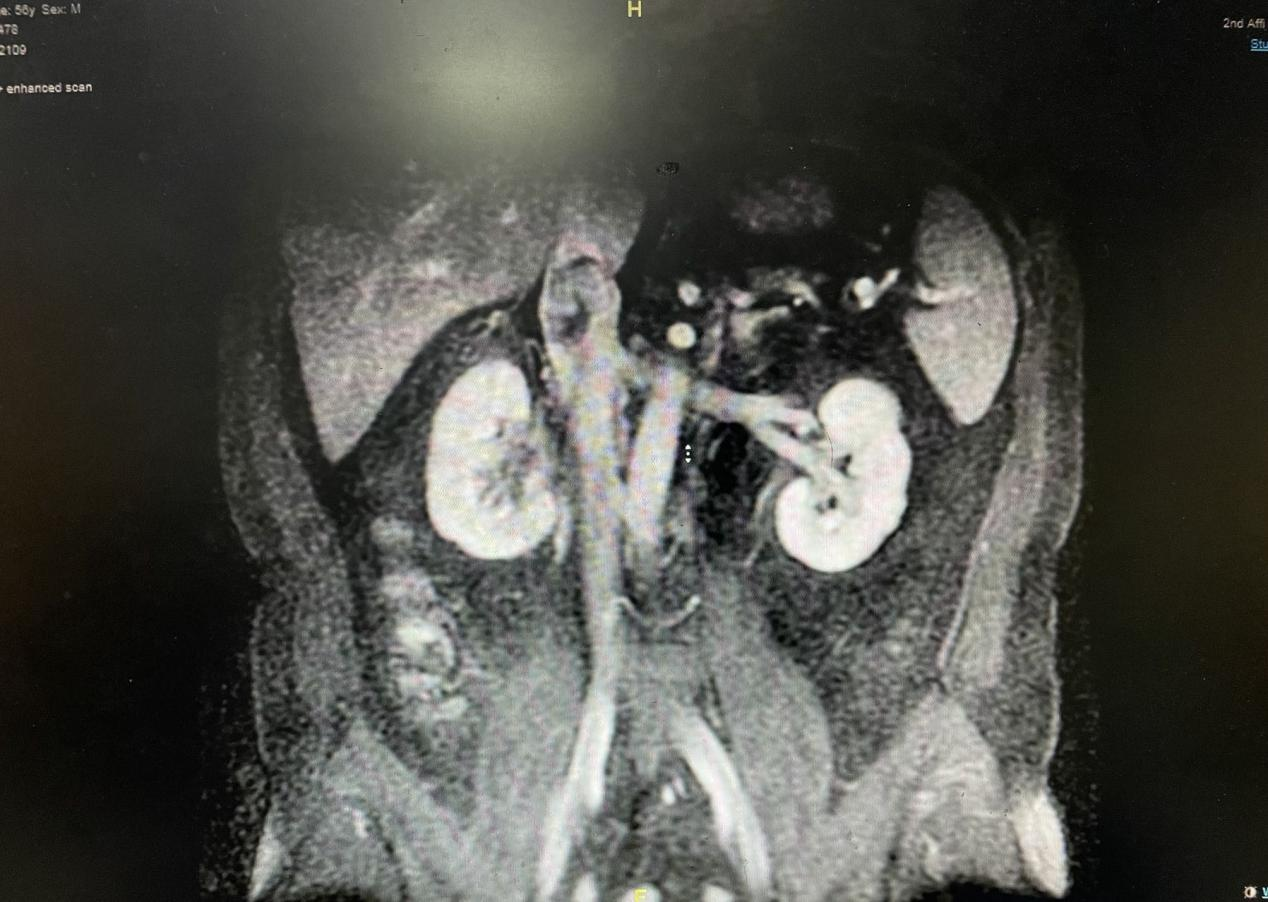

患者为中年男性,因彩超检查发现右肾肿瘤入院。完善检查发现右肾癌并右肾静脉、腔静脉癌栓,下腔静脉癌栓位置高于肝尾状叶,癌栓长度接近 6 cm, 属于 II 级癌栓。明确诊断后,刘飞教授团队决定行肾癌根治性切除并腔静脉癌栓取出术。该手术是泌尿外科最具挑战性的手术,手术难度和风险极大,术中可能存在癌栓脱落引起致命性肺栓塞和大出血的风险。